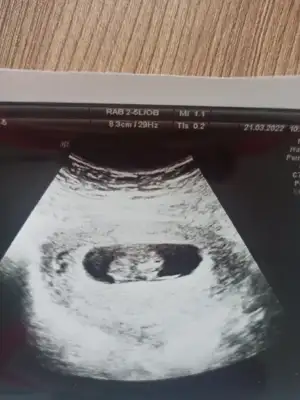

Merhaba 12+5 haftalik, sizce ne olabilir, gecen sormustum size erkek demistiniz, doktor kiz olabilir dedi ama net konusmadi, belli degil henuz tam dedi, sormak istedim🙈size yeniden😊

Karindan ultrason bu arada